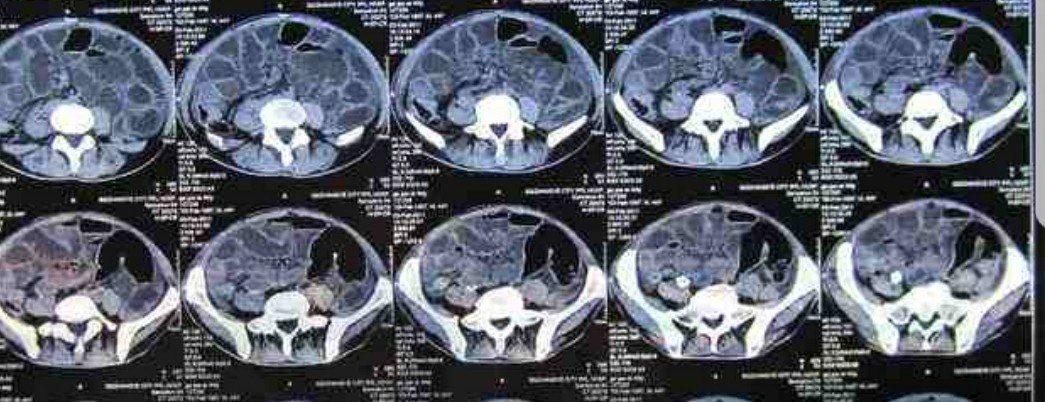

CT、

血、尿常规等检查确诊。